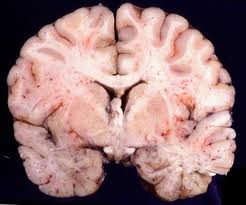

5. CNS

If the CNS is affected by the neonatal herpes simplex virus infection, a year’s mortality rate is about four percent. There is evidence of seizures, near-coma, and prematurity for the affected infants. About 30% of the survivors have normal development of the CNS.